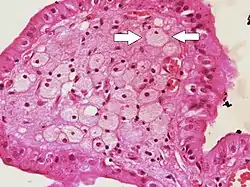

![]() Foam cells (one indicated by arrows) visible in the finger-like projections into the gallbladder lumen in a case of cholesterolosis | |

Foam cells, also called lipid-laden macrophages, are a type of cell that contain cholesterol. These can form a plaque that can lead to atherosclerosis and trigger myocardial infarction and stroke.[1][2][3]

Foam cells are fat-laden cells with a M2 macrophage-like phenotype. They contain low density lipoproteins (LDL) and can only be truly detected by examining a fatty plaque under a microscope after it is removed from the body.[4] They are named because the lipoproteins give the cell a foamy appearance.[5]